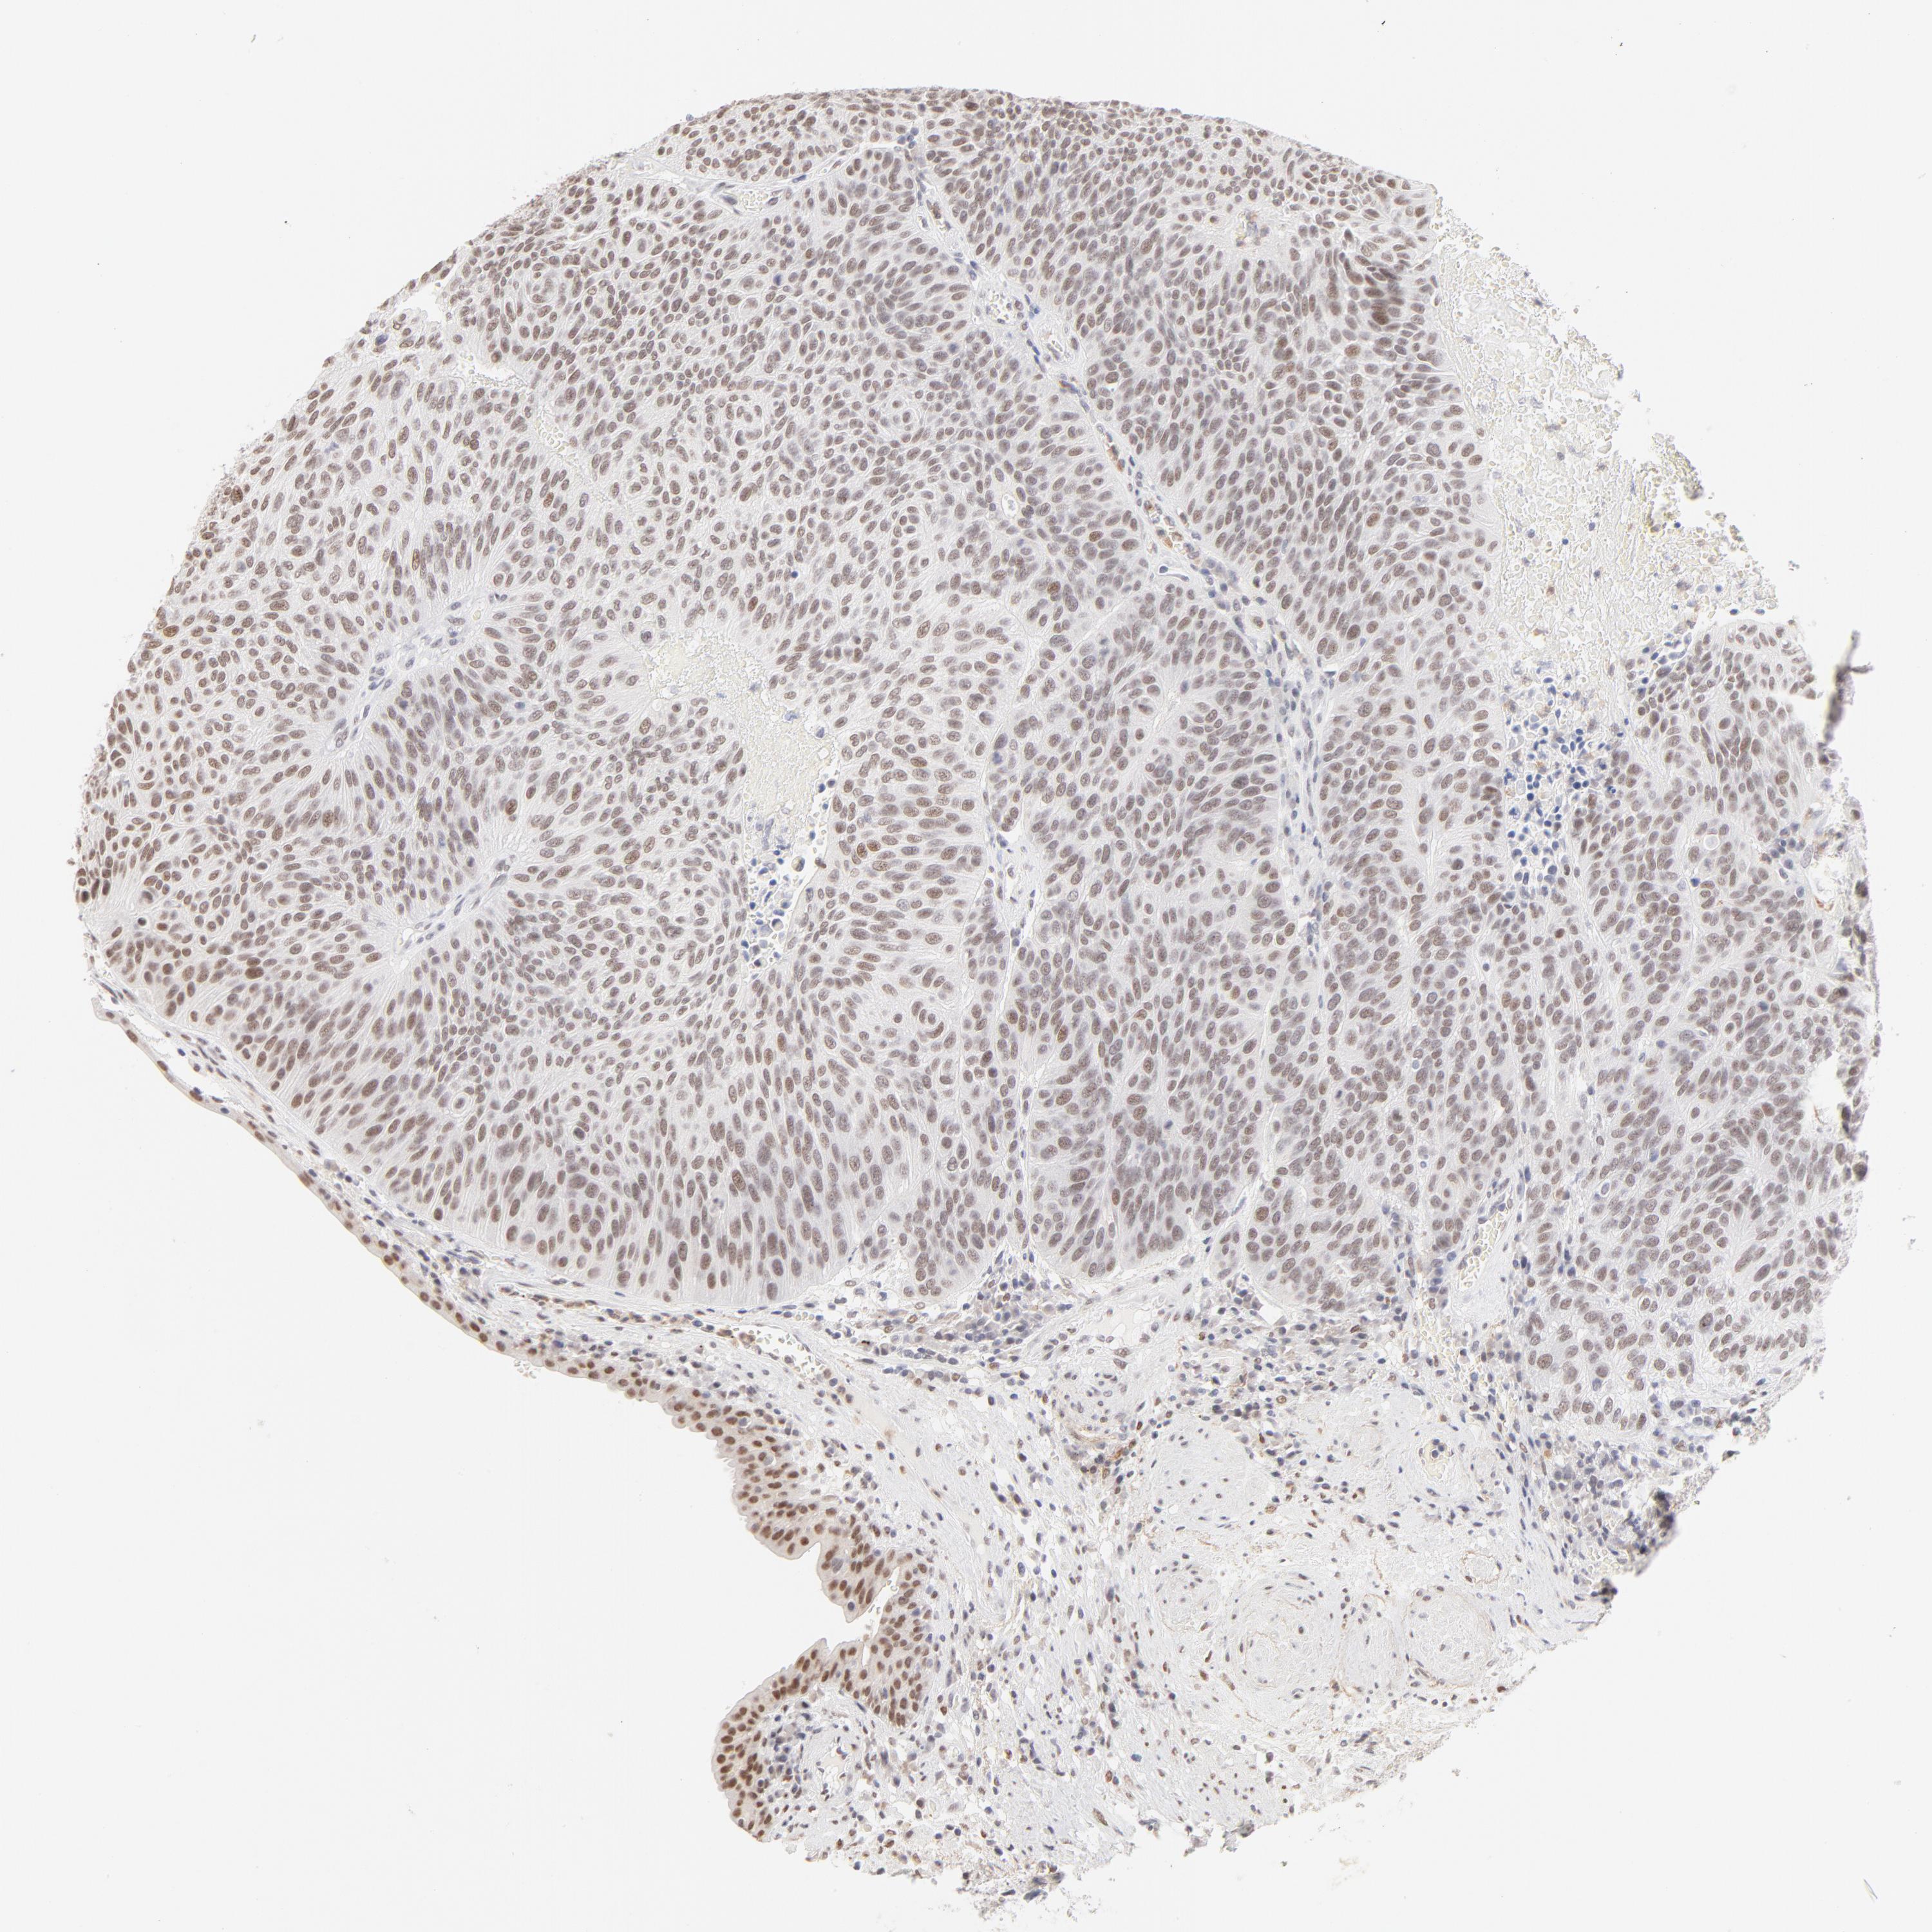

UROTHELIAL CANCER - Protein expressioni

A mouse-over function shows sample information and annotation data. Click on an image to view it in a full screen mode. Samples can be filtered based on level of antibody staining by selecting one or several of the following categories: high, medium, low and not detected. The assay and annotation is described here.

Antibody stainingi

Antibody staining in the annotated cell types in the current human tissue is reported as not detected, low, medium, or high, based on conventional immunohistochemistry profiling in selected tissues. This score is based on the combination of the staining intensity and fraction of stained cells.

Each image is clickable and will lead to virtual microscopy that enables deeper exploration of all samples and also displays staining intensity scores, fraction scores and subcellular localization as well as patient and tissue information for each sample.

Antibody HPA003505

Antibody HPA003881

Antibody CAB018768

Urothelial carcinoma, High grade

Urothelial carcinoma, Low grade